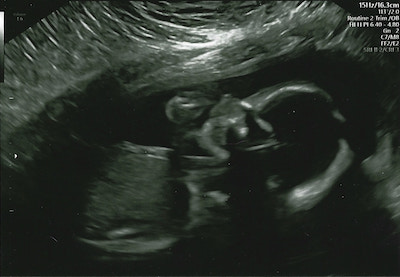

At the 20 weeks mark we found out you were a boy! I can't believe how beautiful you looked, and you were growing like a weed. Currently, you love when mommy eats fruit and you're always pushing me to eat anything that has garlic in it, especially yummy Greek food - which Daddy doesn't like!